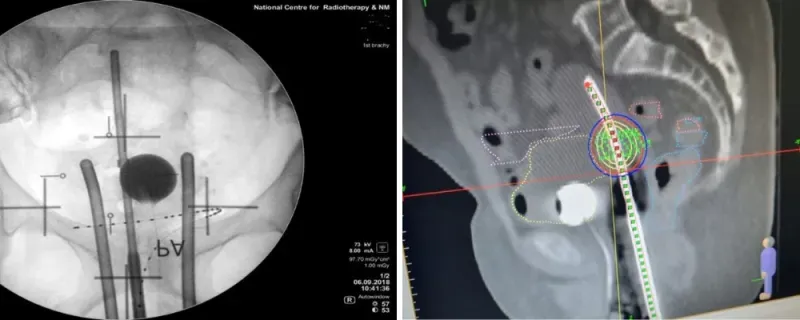

To address these gaps in cervical cancer care, Dr. Scott collaborated with colleagues at PM, learning vital 3D radiotherapy techniques for implementation in Ghana. This prepared her to design a treatment program that can replace older radiotherapy approaches with modern and more effective 3D techniques.

“Prior to this, our patients had for several years been treated with simple 2D treatment techniques, so this program was timely as our department had installed the infrastructure needed for migration from 2D to modern 3D treatment techniques. Hopefully, patients treated at my care center in Ghana will have comparable treatment outcomes as their counterparts in more developed nations,” says Dr. Scott. “With our new program, some of our patients are treated with modern advanced [3D] treatment techniques, which are associated with minimal toxicities and better treatment outcomes compared to the old 2D methods.”

Based on insights from her Conquer Cancer research and collaboration with PM and local mentors, Dr. Scott is including CT scans as part of her home institution’s 3D radiotherapy program. Compared to standard pre-treatment measures like chest-rays and ultrasound, CT scans can provide more detailed information about patients whose disease has multiplied and spread to lymph nodes and other areas of the body. This detection technique helps oncologists more effectively tailor 3D radiotherapy treatment to the unique needs of each patient.